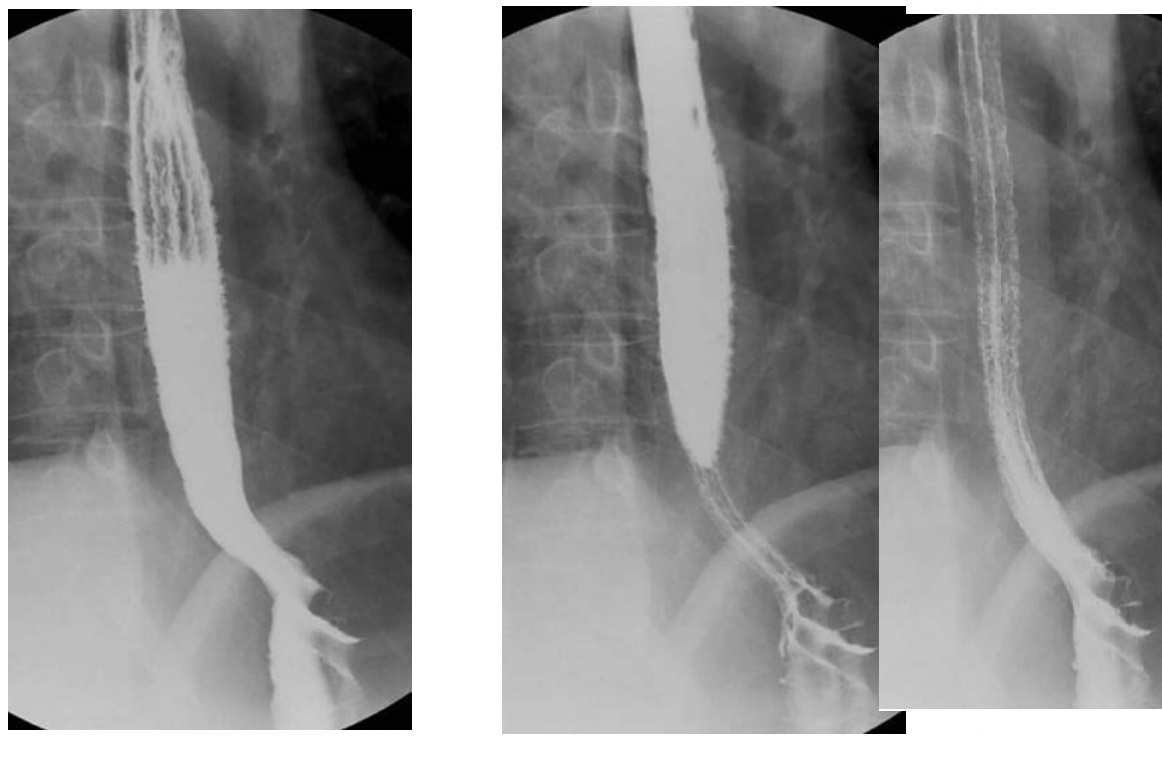

Candidiasis

irregular, longitudinal plaques with intervening normal mucosa

Typically upper 1/3 oesophagus

Immunocompromised (HIV, Transplant)

In older asymptomatic patients = Mucosal white plaques more uniform, rounded, and less well defined than candidiasis = Glycogenic Acanthosis